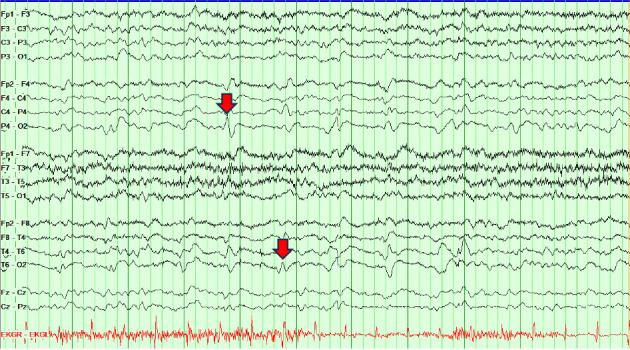

Presenting symptoms of sporadic Creutzfeldt-Jakob disease (sCJD) are variable, and as imaging and EEG may be normal in the early to middle stages of the disease process, serial testing is vital when there is clinical suspicion for sCJD. We present a case of probable Heidenhain variant of sCJD (HvCJD) with notable rapid progression. A 72-year-old woman presented with neurological decline following new-onset visual changes. Over the course of 3 weeks, she developed ataxia followed by paranoia, memory impairment, and visual hallucinations. An extensive workup from 1 week prior at an outside hospital was unrevealing and included two magnetic resonance imaging (MRI) studies read as normal and an EEG without periodic sharp wave complexes. Repeat of imaging at our hospital showed cortical restricted diffusion in the right occipital lobe. In combination with new periodic sharp wave complexes visualized on prolonged EEG, concern was raised for sCJD. Palliative care was consulted early in the hospitalization, and the patient was transitioned to comfort care and discharged 3 days after admission. She declined quickly and passed away at home within a week, one day before her send out CSF sample resulted with a positive real-time quaking-induced conversion (RT-QuiC) and markedly elevated T-tau protein and 14-3-3 gamma. As there is no treatment for this fatal disease, palliative engagement and discussion of goals of care in cases of CJD is critical in providing compassionate care for the patient and their family. High clinical suspicion warrants discussion of comfort care measures even prior to confirmation with RT-QuiC.